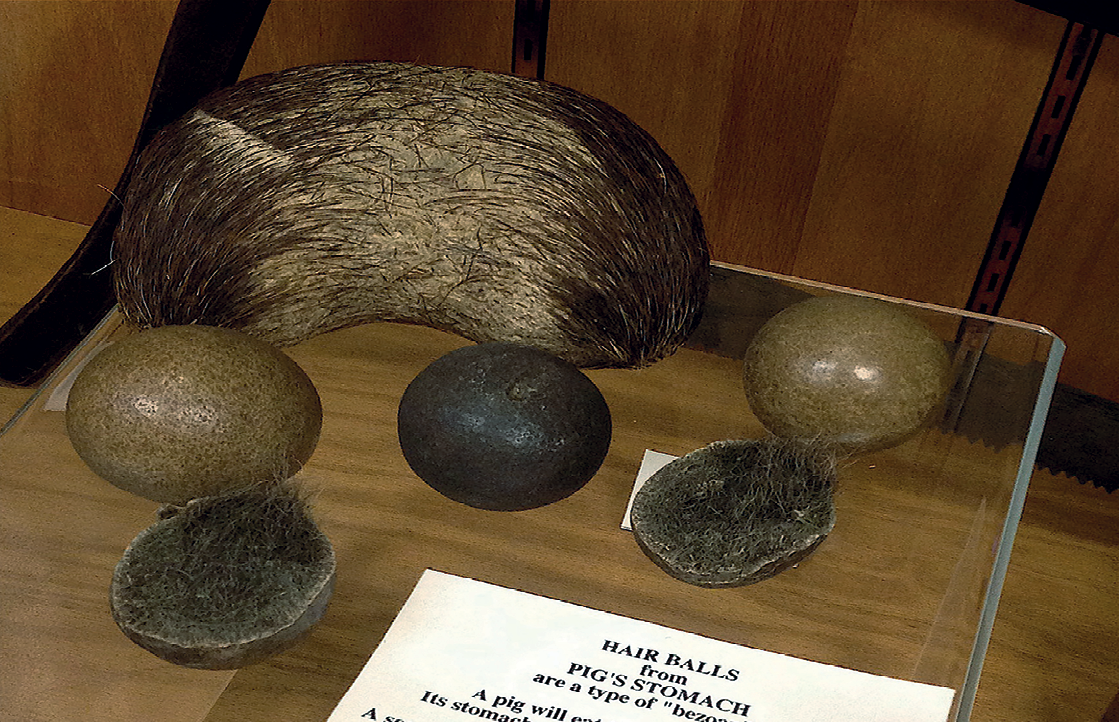

La palabra bezoar se deriva del arabe “panzehr” y del persa “padzahr”, que significan en ambos casos antídoto (expulsar veneno), a los cuales se les otorgaban propiedades protectoras principalmente contra envenenamientos. Los bezoares son concreciones o masas de materia, se definen como conglomerados de materiales no comestibles o no digeridos -ingeridos voluntaria o involuntariamente- que se retienen en el tracto gastrointestinal y son incapaces de transitar a través de éste1-3.

Los bezoares pueden estar conformados por una gran variedad de materiales y, de acuerdo con su composición, generalmente se clasifican en 4 tipos1-3:

Tricobezoares: Compuestos de cabello. Es una condición poco común y se diagnostica generalmente en mujeres jóvenes. Se asocia principalmente a patología psiquiátrica y a tricofagia1-3.

Actualmente se reconoce un quinto grupo, los polibezoares, que se forman de una amplia gama de materiales ingeridos como metales y plástico4,5.

Pueden existir otros tipos de bezoares de diferente etiología, y se pueden categorizar como atípicos3. Su composición puede incluir plástico, metales, gusanos-parásitos, papel, productos textiles y en general cualquier producto no digerible que pueda causar una formación de masa con secreciones mucosas y alimentos semidigeridos1.